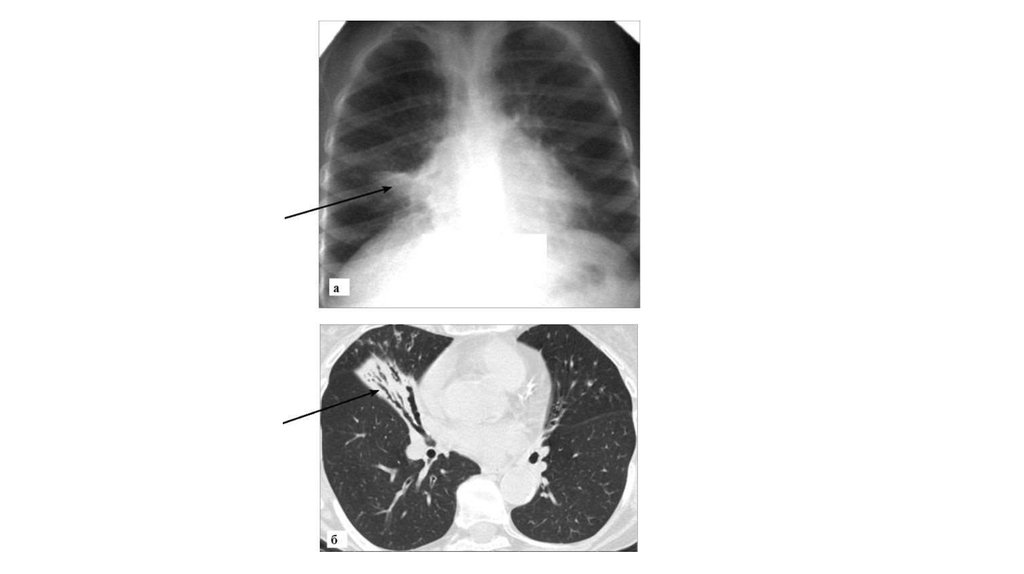

• Идиопатический легочный фиброз:

а - рентгенограмма в прямой проекции. Двустороннее усиление и

сетчатая деформация легочного рисунка, объемное уменьшение

базальных отделов легких, высокое стояние диафрагмы